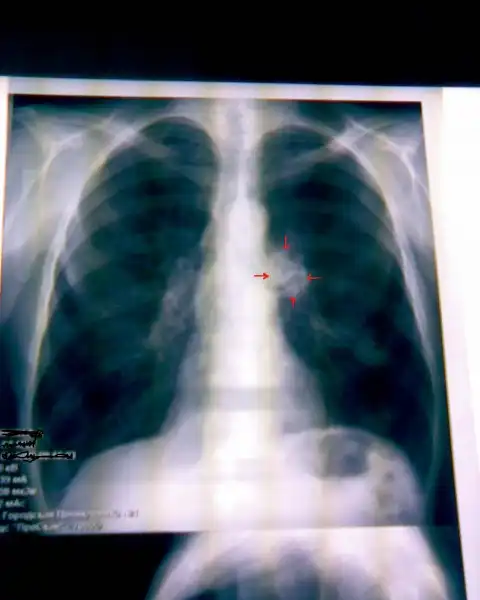

Рак легких в рентгеновском изображении

НОРМА: